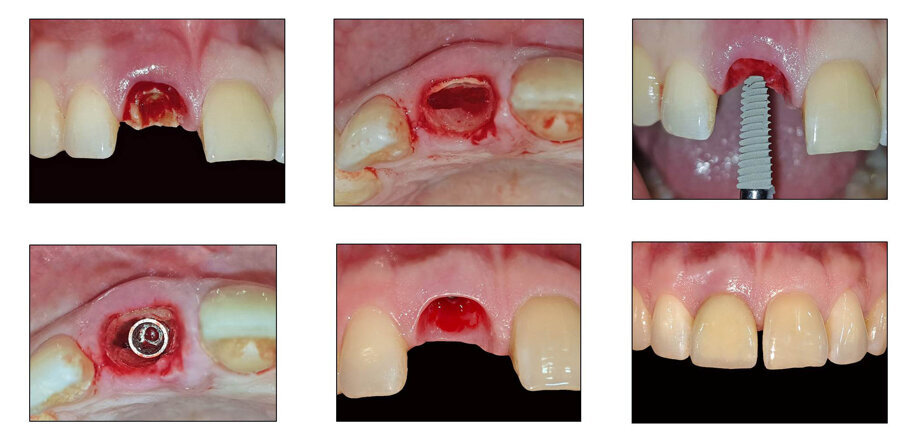

The primary indication for tooth extraction was a fracture of the crown at the cervical region. Without lifting a mucoperiosteal flap or affecting the marginal gingiva, the fractured portion of the tooth was carefully removed. A 1–2mm thick tooth fragment in the buccal area of the extraction socket was separated from the rest of the tooth using Zekrya 28 bur (Strauss) with saline + ciprofloxacin irrigation.

Special precautions were taken to avoid damage to the bone walls of the extraction socket. Following preparation of the implant bed in the palatal part of the root, all residual tooth fragments were completely removed. A careful curettage of the extraction socket was performed to remove granulation tissue. The buccal fragment of the root was preserved 1mm coronal to the buccal bone plate. The 4X13mm implant was placed in the palatal part of the extraction socket, without contact with the labial root portion (shield). 45 Ncm Torque was achieved at the time of implant placement. (Fig 1 - 17)

Fig 7: Removal of the mobile crown fragment

Fg 8: Baseline after the removal of mobile crown fragment

Fig 9: Zekrya 28 bur used for the shield preparation

Fig 10: Splitting the root into buccal and palatal fragments

Fig 11: After sectioning of the root

Fig 12: Removal of the palatal fragment

Fig 13: Removed palatal fragment

Fig 14: Socket components

Fig 15: Osteotomy done on the palatal wall to receive a 4 x13 mm implant

Fig 16: Implant placed at 45 Ncm